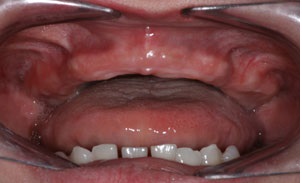

Khi tự điều trị bằng kháng sinh và thấy hết đau chưa hẳn đã khỏi bệnh. Bệnh vẫn tồn tại và trở thành mạn tính, thỉnh thoảng sẽ bộc phát cơn cấp tính (tái diễn theo chu kỳ và ngày càng trầm trọng). Nếu bạn chỉ mới bị viêm nướu, tình trạng đó sẽ khiến bạn chuyển nhanh sang giai đoạn bệnh viêm nha chu. Nếu đã bị viêm nha chu thì bệnh sẽ ngày càng trầm trọng, làm răng lung lay nhiều hơn, cuối cùng là mất răng.

Để phòng bệnh nha chu, theo Bác sĩ Võ Văn Nhân: điều quan trọng nhất là đánh răng đều đặn sau các bữa ăn và trước khi đi ngủ để loại bỏ mảng bám vi khuẩn trên bề mặt răng và khe nướu, đảm bảo được sức khỏe răng miệng. Định kỳ 3-6 tháng nên đến khám răng định kỳ tại các phòng khám chuyên khoa răng hàm mặt và lấy sạch vôi răng, mảng bám ở những nơi bàn chải không làm sạch được. Việc cạo vôi răng sẽ giúp: phòng ngừa được bệnh nha chu; có hàm răng sạch, bóng và đẹp; tự tin hơn trong giao tiếp hằng ngày.